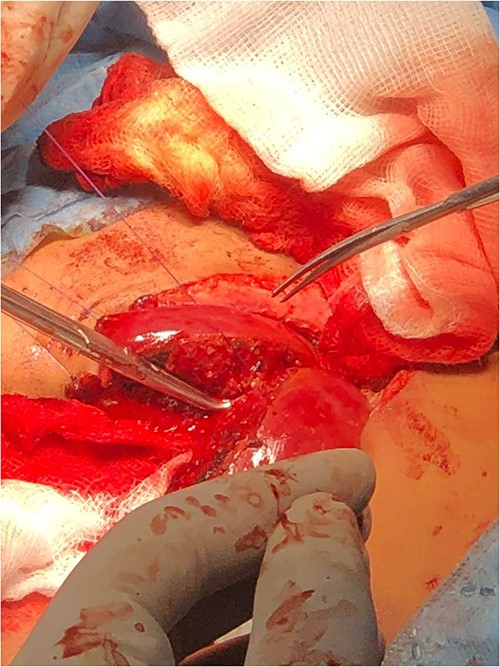

Following the placement of central lines, the two babies were anathesized and stabilized with vital sign monitoring and fluid adjustments. Then, using monopolar and bipolar diathermy, incisions and flaps were made until the peritoneum, where complete fusion of the liver with a sinusoidal connection was discovered. The connected surface area is ⁓8 by 6 cm, primarily in the caudal lobe, whereas twins B has one lobe liver and one gall bladder (Fig. 4). The xiphoid process, sternum, pleura and pericardium were all visible in the patient and were successfully separated. To avoid the occurrence of compartment syndrome, the abdomen was left as a shallow cavity with only skin closed as a neonatal hernia, then hemostasis was secured via PDS sutures and drains were placed, admitted to neonatal intensive care unit and received blood and fresh frozen plasma. The patients recovered well from anesthesia on the second day, were taken off mechanical ventilation with normal vital signs, and began Nasogastric tube tube feeding 48 h later. Patients began to gain weight and were discharged the next day to be seen at a referral clinic.